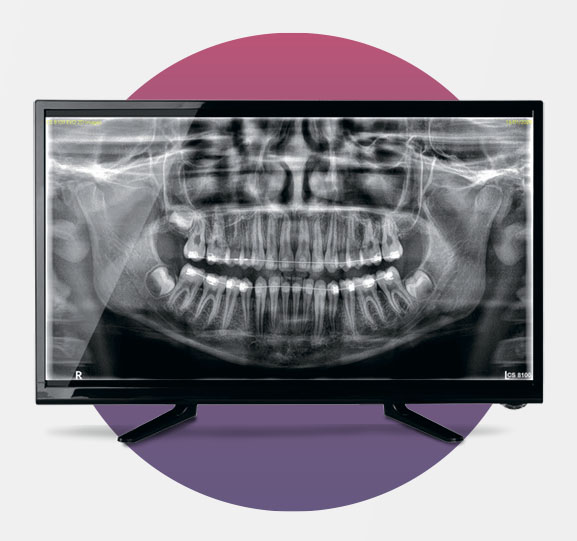

На выставке Dental Salon 2025мы познакомились с возможностями Carestream CS 8100 3D, который идеально подошел под наши задачи: оптимальное сочетание качества, размеров исследования и цены. Дополнительный плюс — нам давно знакома продукция Kodak-Trophy (все прицельные снимки мы делаем на RVG этой марки), а выбранный аппарат выпускается на том же заводе под Парижем. Демонстрация возможностей CS 8100 3D от специалистов UNIDENT произвела на меня сильнейшее впечатление.

Изначально мы не планировали покупать томограф прямо на выставке, мой энтузиазм убедил генерального директора принять решение сразу. Вскоре аппарат уже был смонтирован, и качество первых снимков подтвердило правильность выбора. Врачи были в восторге от полученных результатов исследований и возможностей нового томографа.

— Качество изображения в стоматологии решает все. Если снимок мутный или есть наложения слоев, врачу приходится напрягать зрение, перепроверять, отправлять пациента на дополнительные снимки. Мы даже использовали ИИ, чтобы уточнить детали на изображении.

А для врачей стало еще удобнее: все 2D-и 3D-изображения хранятся в одной карточке пациента, доступ к ним моментальный. Раньше приходилось загружать разные программы, тратить время на поиск исследований. С новым аппаратом это в прошлом. Можно сказать, что теперь наше стоматологическое зрение стало стопроцентным.

CS 8100 формирует изображения впечатляющей четкости и контрастности благодаря новым алгоритмам Tomosharp и передовым технологиям обработки снимков.

Оборудование формирует четкие и детальные изображения, а процесс обучения минимален. Получить панорамное изображение еще никогда не было так просто!